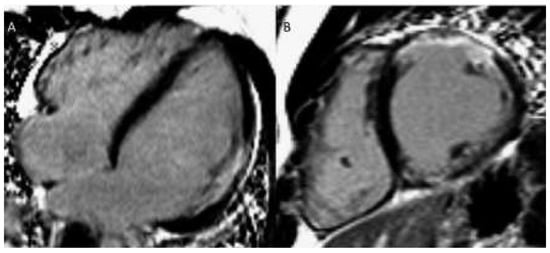

In infants / small children, spatial resolution can be increased by reducing the size of the voxels and increasing signal averages for more signal. For adequate recovery between inversion pulses, acquisition of every third of four heart beats (instead of every other heart beat) should be considered. Image acquisition should be kept short by using a turbo factor to avoid blurring. Reporting: left ventricle 17 segment model, right ventricle 9 segment model [28, 29] (for examples see Figure 4a,b).

Figure 4.

(a) Late gadolinium enhancement (LGE). 21-year-old patient with arterial switch for transposition of the great arteries (TGA) after postoperative myocardial ischaemia. Extensive area with subendocardial LGE in anterolateral segment (A) and in the inferior mid-ventricular segment (B). (b) Patient with transannular patch repair and VSD closure for tetralogy of Fallot and residual severe PR. LGE in RVOT aneurysm (A), LGE of the RVOT aneurysm and VSD patch area and inferior insertion point (RV hypertrophy) (B), LGE in the RV free wall (C−D).